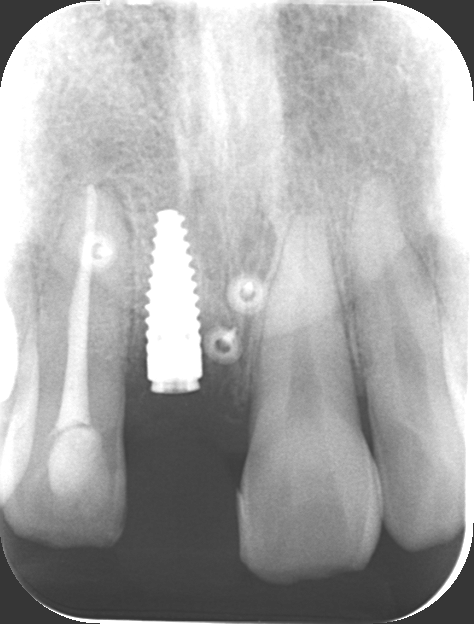

前歯が腫れてしまったと来院された患者様です。

レントゲンを見てみると歯根(歯の根の部分)が黒く溶けていることが分かり、抜歯と診断しました。

前歯のインプラントはとても難しく技術がないと歯茎が下がってしまったりと不具合が出てしまいます。

X-ray

処置後、非常に審美的な補綴物が入ったことが分かるかと思います。

| 治療期間 | 1年6か月 |

|---|---|

| 費用 | インプラント 37万円 骨造成 15万円 補綴 ジルコニアクラウン 15万円 |